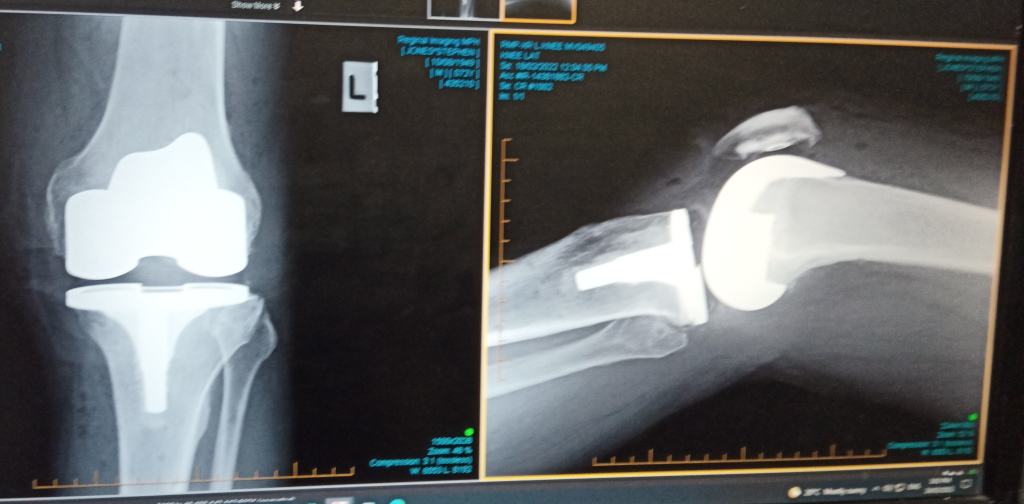

This X-ray shows the same knee a few weeks after having a knee replacement. Most of the patella has also been replaced with a plastic one. If you wear the artificial cartilage out they can replace it. Just a pity they can’t do the same with the natural cartilage – something I was waiting to happen – perhaps your generation will see such improvements. I am just lucky they have been able to do this for me and that I am (now) able to walk again without pain.